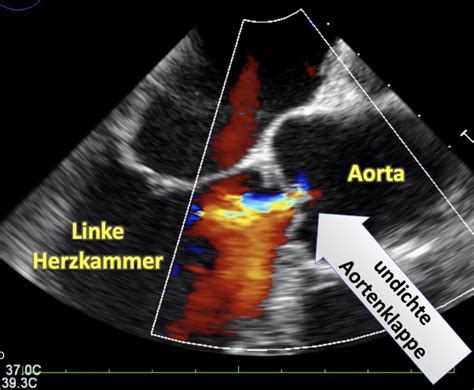

Die wichtigste Untersuchungsmethode bei einem Verdacht auf ein PFO ist die Echokardiographie, eine Ultraschalluntersuchung des Herzens. Es gibt verschiedene Formen der Echokardiographie, die zur Diagnose eingesetzt werden:

Bei der transösophagealen Echokardiographie (Schluckecho) wird die Ultraschallsonde über die Speiseröhre vorsichtig bis auf Höhe des Herzens vorgeschoben. Diese Methode bietet eine sehr gute Bildqualität und ermöglicht eine genaue Darstellung des PFO. Oft wird während der Untersuchung eine Kontrastlösung verabreicht, um den Blutfluss durch das PFO sichtbar zu machen. Die Untersuchungsdauer beträgt in der Regel 15 bis 45 Minuten.